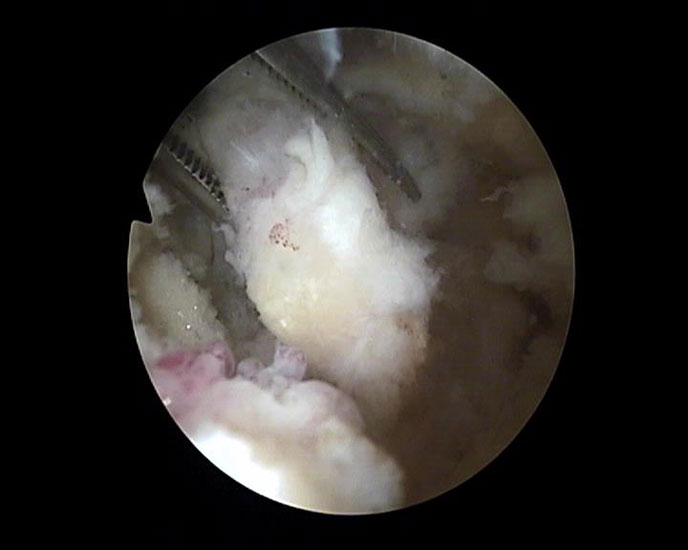

Abbildung Nr. 8-10

Es wird zunächst ein Weichteildebridement durchgeführt, bis die Flexor hallucis longus-Sehne identifiziert werden kann. Während des Debridements sollte auf die korrekte Ausrichtung der Instrumentenöffnung nach lateral geachtet werden. Im Verlauf empfiehlt sich der Wechsel auf eine bipolare Ablationselektrode, die eine gezielte Freilegung der Strukturen unter gleichzeitiger Blutstillung ermöglicht, ohne dabei unkontrolliert Gewebe anzusaugen (rechte Seite, m=medial, l=lateral). Das Os trigonum bzw. die Osteophyten sowie die FHL-Sehne müssen vollständig dargestellt werden (*=Os trigonum, FHL=Flexor hallucis longus-Sehne).